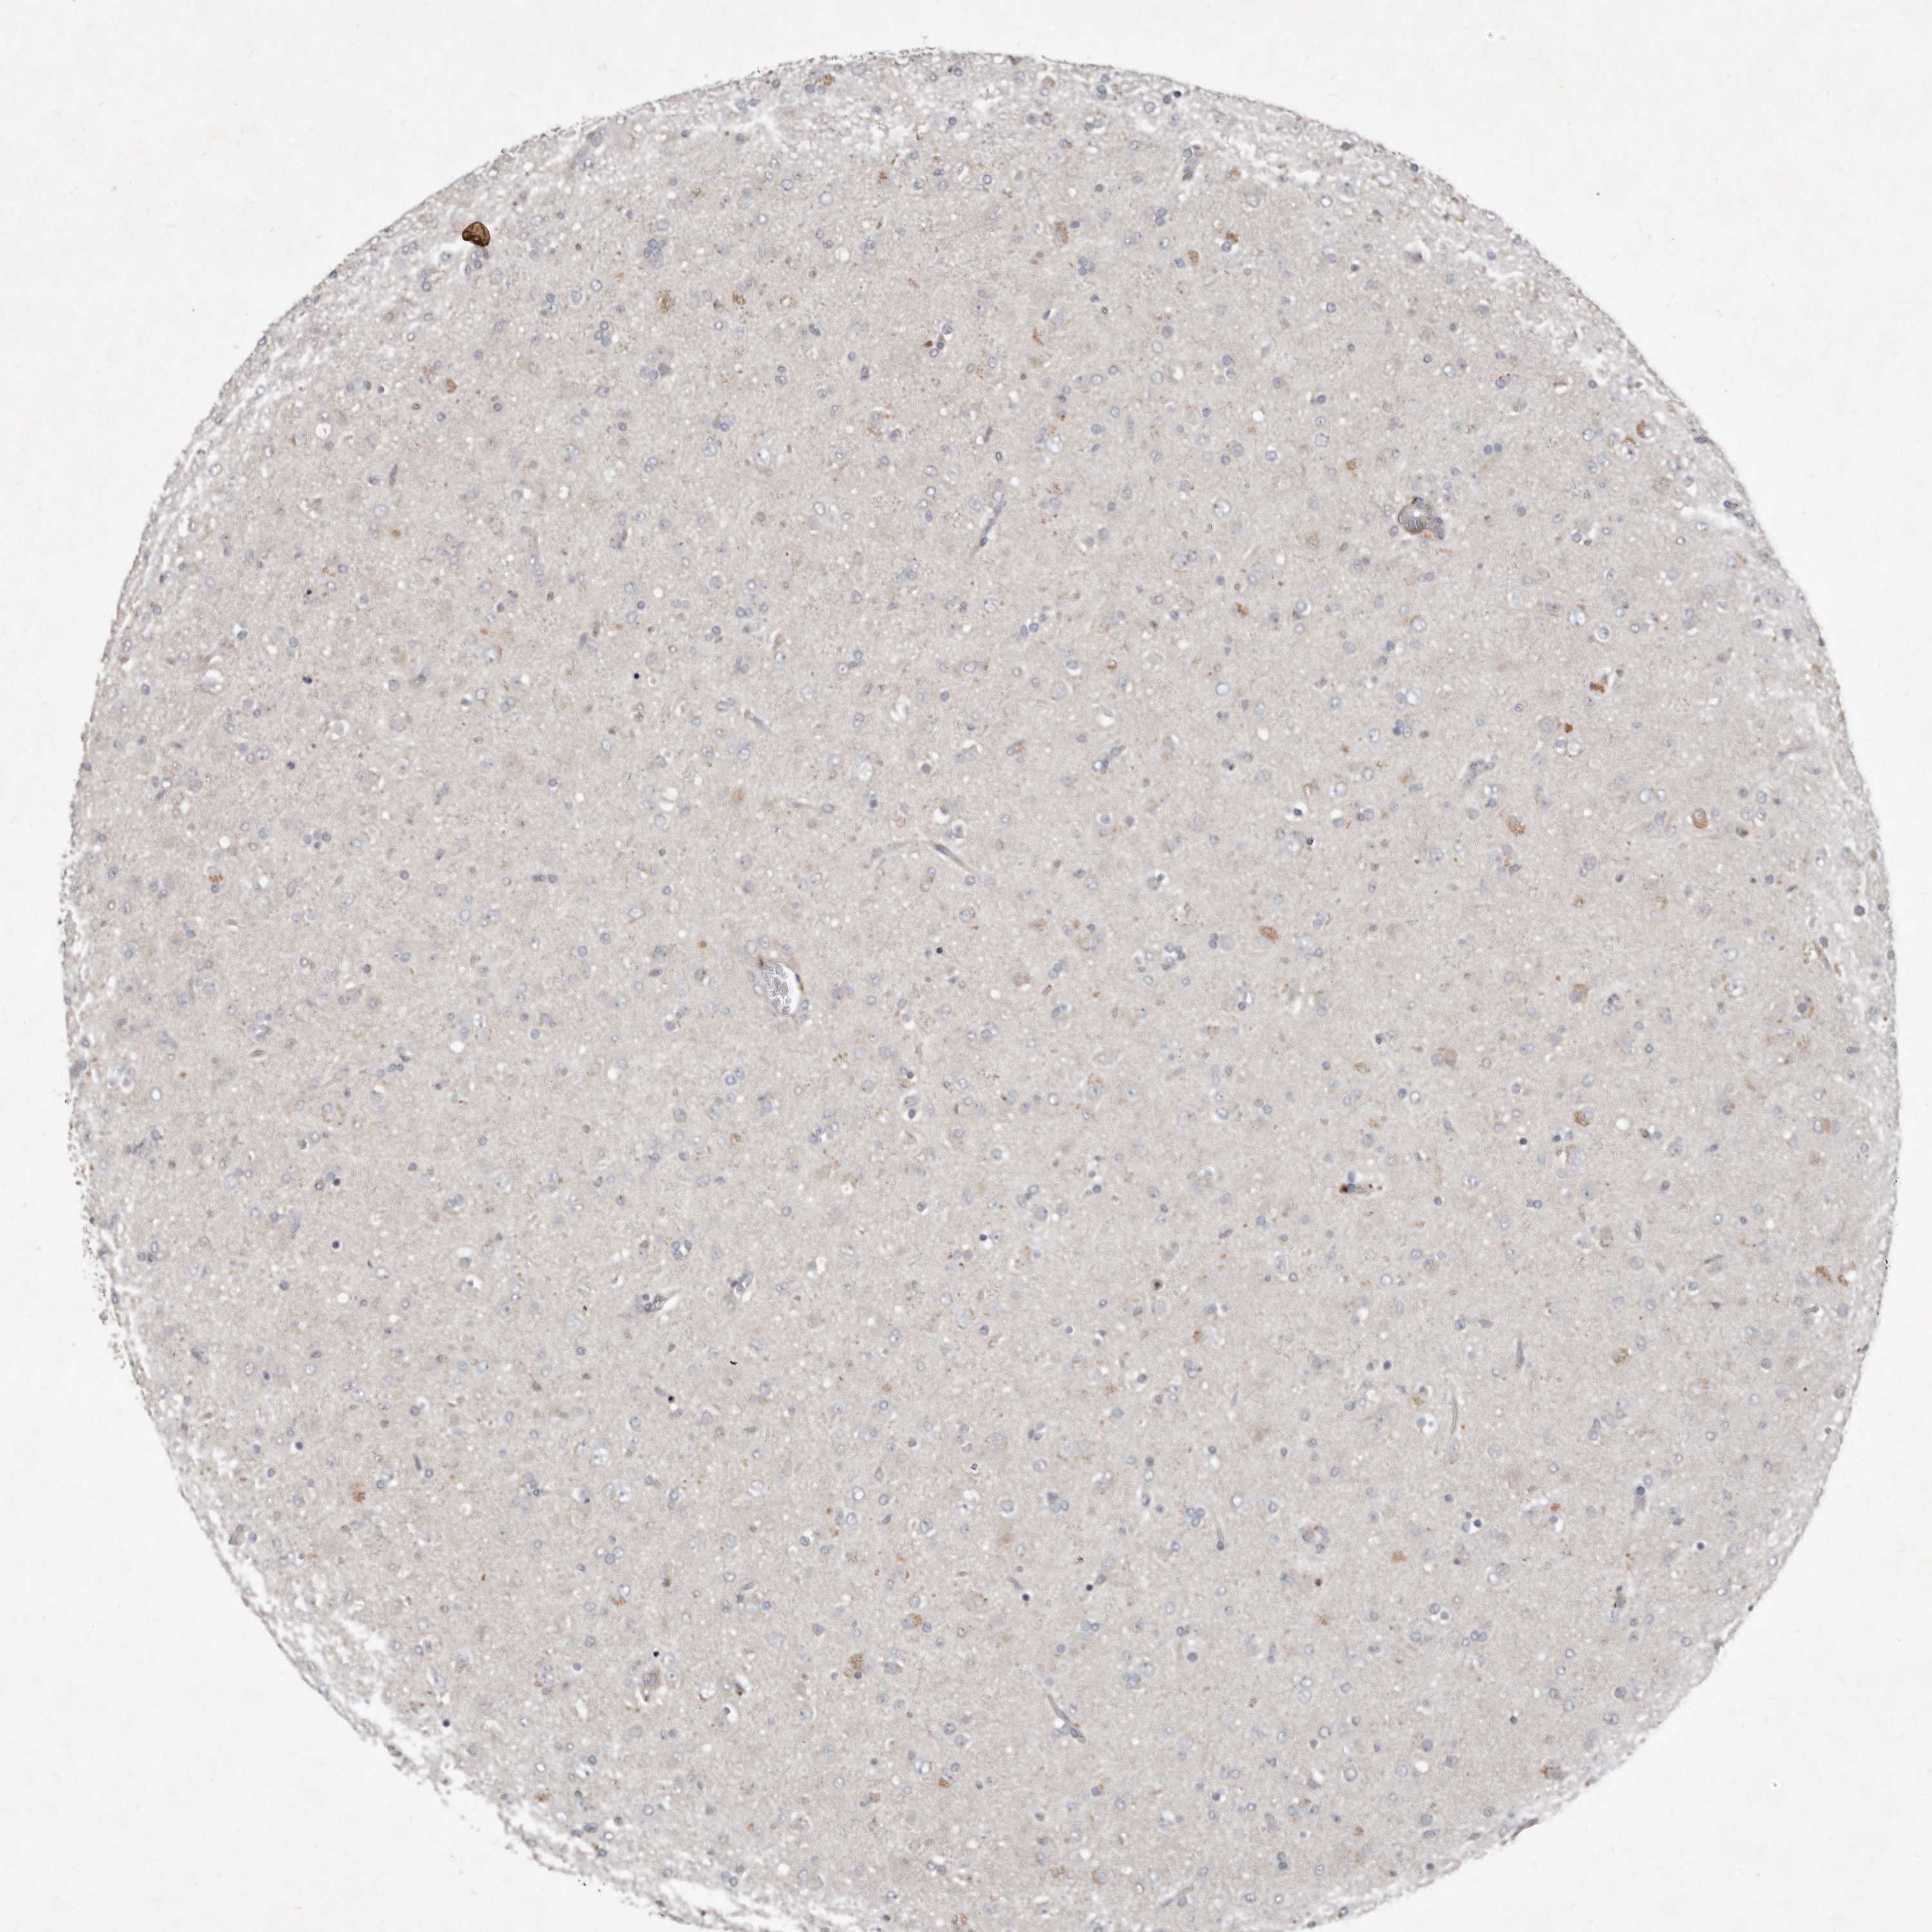

GLIOMA - Protein expressioni

A mouse-over function shows sample information and annotation data. Click on an image to view it in a full screen mode. Samples can be filtered based on level of antibody staining by selecting one or several of the following categories: high, medium, low and not detected. The assay and annotation is described here.

Note that samples used for immunohistochemistry by the Human Protein Atlas do not correspond to samples in the TCGA dataset.

Antibody stainingi

Antibody staining in the annotated cell types in the current human tissue is reported as not detected, low, medium, or high, based on conventional immunohistochemistry profiling in selected tissues. This score is based on the combination of the staining intensity and fraction of stained cells.

Each image is clickable and will lead to virtual microscopy that enables deeper exploration of all samples and also displays staining intensity scores, fraction scores and subcellular localization as well as patient and tissue information for each sample.

Antibody HPA030270

Antibody HPA030271

Antibody HPA030272

Staining

High

Medium

Low

Not detected

Intensity

Strong

Moderate

Weak

Negative

Quantity

>75%

75%-25%

<25%

None

Location

Nuclear

Cytoplasmic/membranous

Cytoplasmic/membranous,nuclear

Glioma, malignant, High grade

Glioma, malignant, Low grade

Glioblastoma, NOS